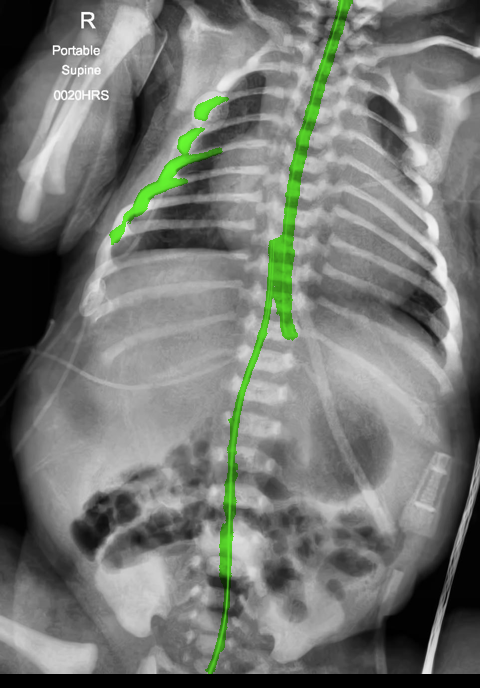

There are certain situations where our proposed method would fail. Figure 7 (a) and (b) show a partially detected NGT. This mostly likely resulted from the decreased visibility of the radiopaque strip. Figure 7 (a) also shows another failure situation where the inferior portion of the UVC is occluded by the abdomen. (c) shows the case of a falsely detected unidentified line and (d) shows part of the lateral aspect of the rib cage falsely identified as a catheter.